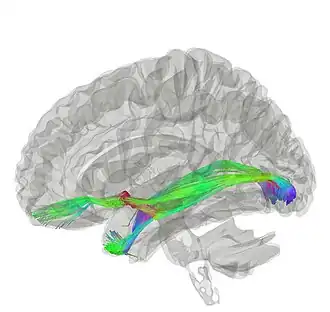

![]() Tractography of anterior commissure | |

The anterior commissure (also known as the precommissure) is a white matter tract (a bundle of axons) connecting the two temporal lobes of the cerebral hemispheres across the midline, and placed in front of the columns of the fornix. In all but five species of mammal the great majority of fibers connecting the two hemispheres travel through the corpus callosum, which in humans and all non-monotremes is more than 10 times larger than the anterior commissure. Other routes of communication pass through the hippocampal commissure or, indirectly, via subcortical connections. Nevertheless, the anterior commissure is a significant pathway that can be clearly distinguished in the brains of all mammals.

It interconnects multiple cortical regions of the temporal lobes, the amygdalae, and olfactory bulbs.[1] It is a part of the neospinothalamic tract for pain.

The functionality of the anterior commissure is still not completely understood. Researchers have implicated it in functions ranging from colour perception to attention. One such study supported colour perception in callosal agenesis (those born without a corpus callosum; Barr & Corballis, 2002).[3] Other studies have built on this to imply that the anterior commissure can be a compensatory pathway in those without a corpus callosum, presenting diffusion tensor imaging (DTI) techniques to better elucidate the anterior commissure and how it might be implicated in various functions (Winter & Franz, 2014).[2]